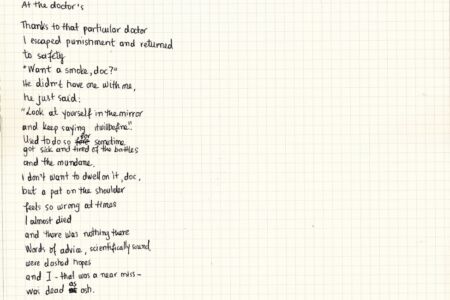

Οι εικόνες της σειράς αυτής μαζί με τα χειρόγραφα ποιήματα δημιουργήθηκαν κατά την διάρκεια μιας σκοτεινής περιόδου έξι χρόνων. Η σειρά αποτελεί μια καταγραφή σκέψεων και αναμνήσεων, πιθανόν μια διαδρομή προς κάτι σημαντικό.

The pictures in these series along with the handwritten poems had been created over a period of six dark years and it ended up as a diary of thoughts and memories, possibly a journey towards something meaningful.

It is an attempt to chart my path through mental illness such as a major depressive disorder. It is a description of fighting against it and mourning. I know that there will always be relapses of the disease but I am aware now, I embraced it to the point I can celebrate and thrive over my fears. I also want these series to be a liberation of the stigma and prejudice that follow people who suffer from mental illness. Being mentally ill is a medical condition and it should never be related to weakness.